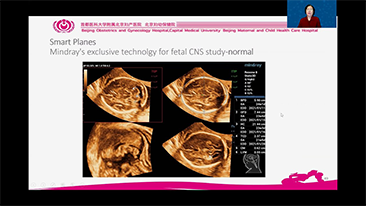

Supportata dalla piattaforma avanzata ZST+, la gamma completa di soluzioni smart di Nuewa ├© progettata appositamente per migliorare la salute della donna durante il periodo pre-gravidanza, la gravidanza e il recupero post-parto, per fornire diagnosi complete ed efficaci e per rispondere a sfide cliniche sempre pi├╣ impegnative.